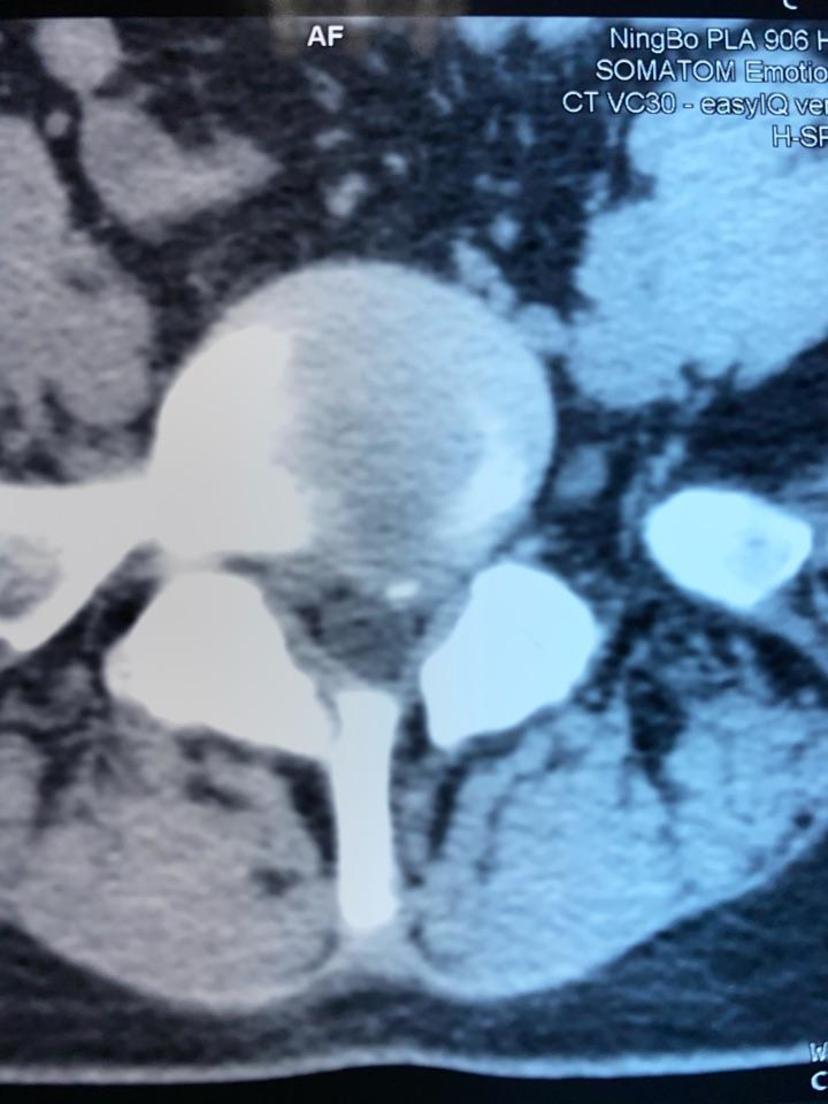

CT显示突出钙化的椎间盘压迫左侧神经根